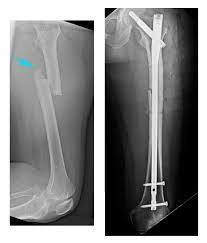

The method used to fix long bone (femur, tibia, humerus) fractures?

Intramedullary nail

* it allows early mobilisation